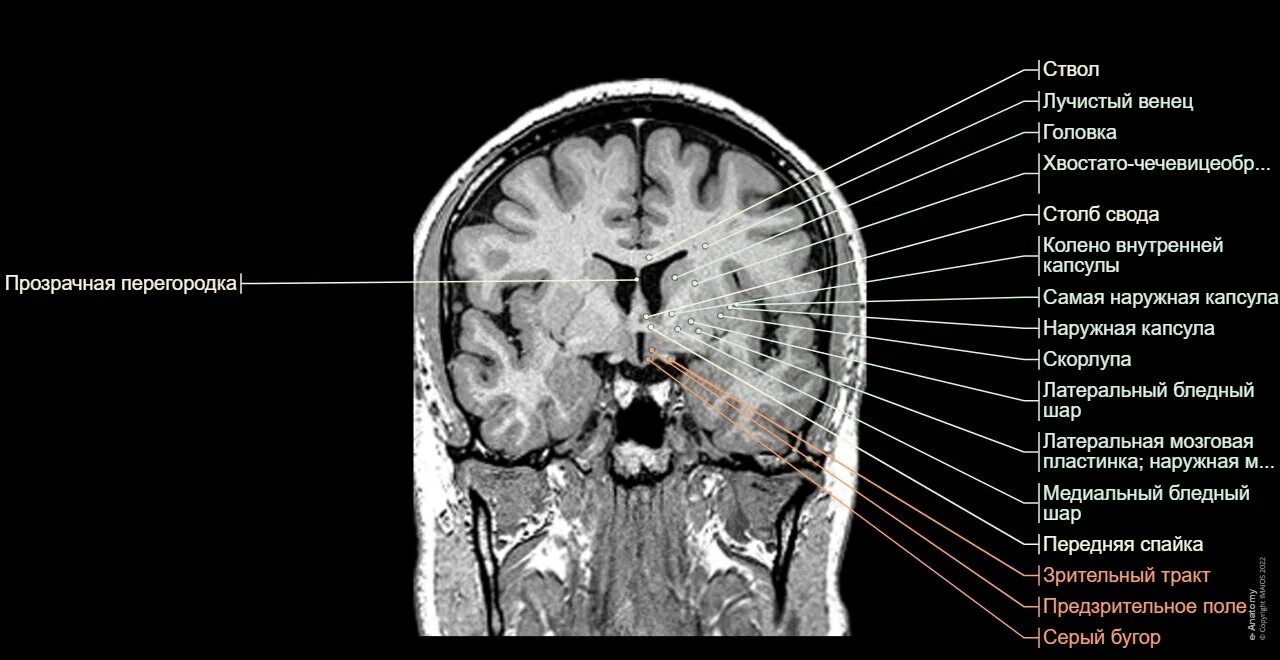

Атлас кт мрт